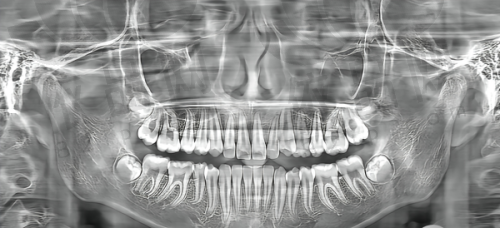

你是否好奇在南京鼓楼看牙的费用情况?今天就为大家揭秘2024年南京鼓楼各口腔医院的价格,涵盖矫正、镶牙、种牙等多项费用。

这份南京鼓楼各口腔医院价格表详细地展示了各类看牙项目的费用,不仅能让你了解看牙是否昂贵,还能帮助你提前知晓种植牙、牙齿矫正、镶牙等具体花费,是不是特别有参考价值呢?